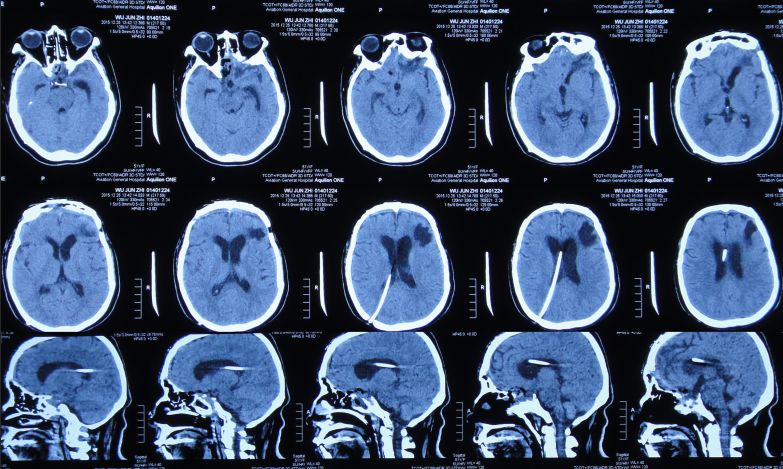

拔除头部侧脑室外引流管后第2天即2015年8月3日,患者仍有脑脊液鼻漏,再次出现发热、头痛症状;复查头CT:脑室较前扩张,室旁水肿明显,颅内积气(图14),医生给予甘露醇脱水治疗。

![]()

图14:2015年8月3日头CT:脑室较前扩张,室旁水肿明显,颅内积气

2015年8月6日,复查头CT:脑室显著扩张,室旁水肿明显,颅内积气(图15)。患者仍有脑脊液鼻漏,但当地医院不予脑脊液漏修补治疗。

图15:2015年8月6日头CT:脑室显著扩张,室旁水肿明显,颅内积气